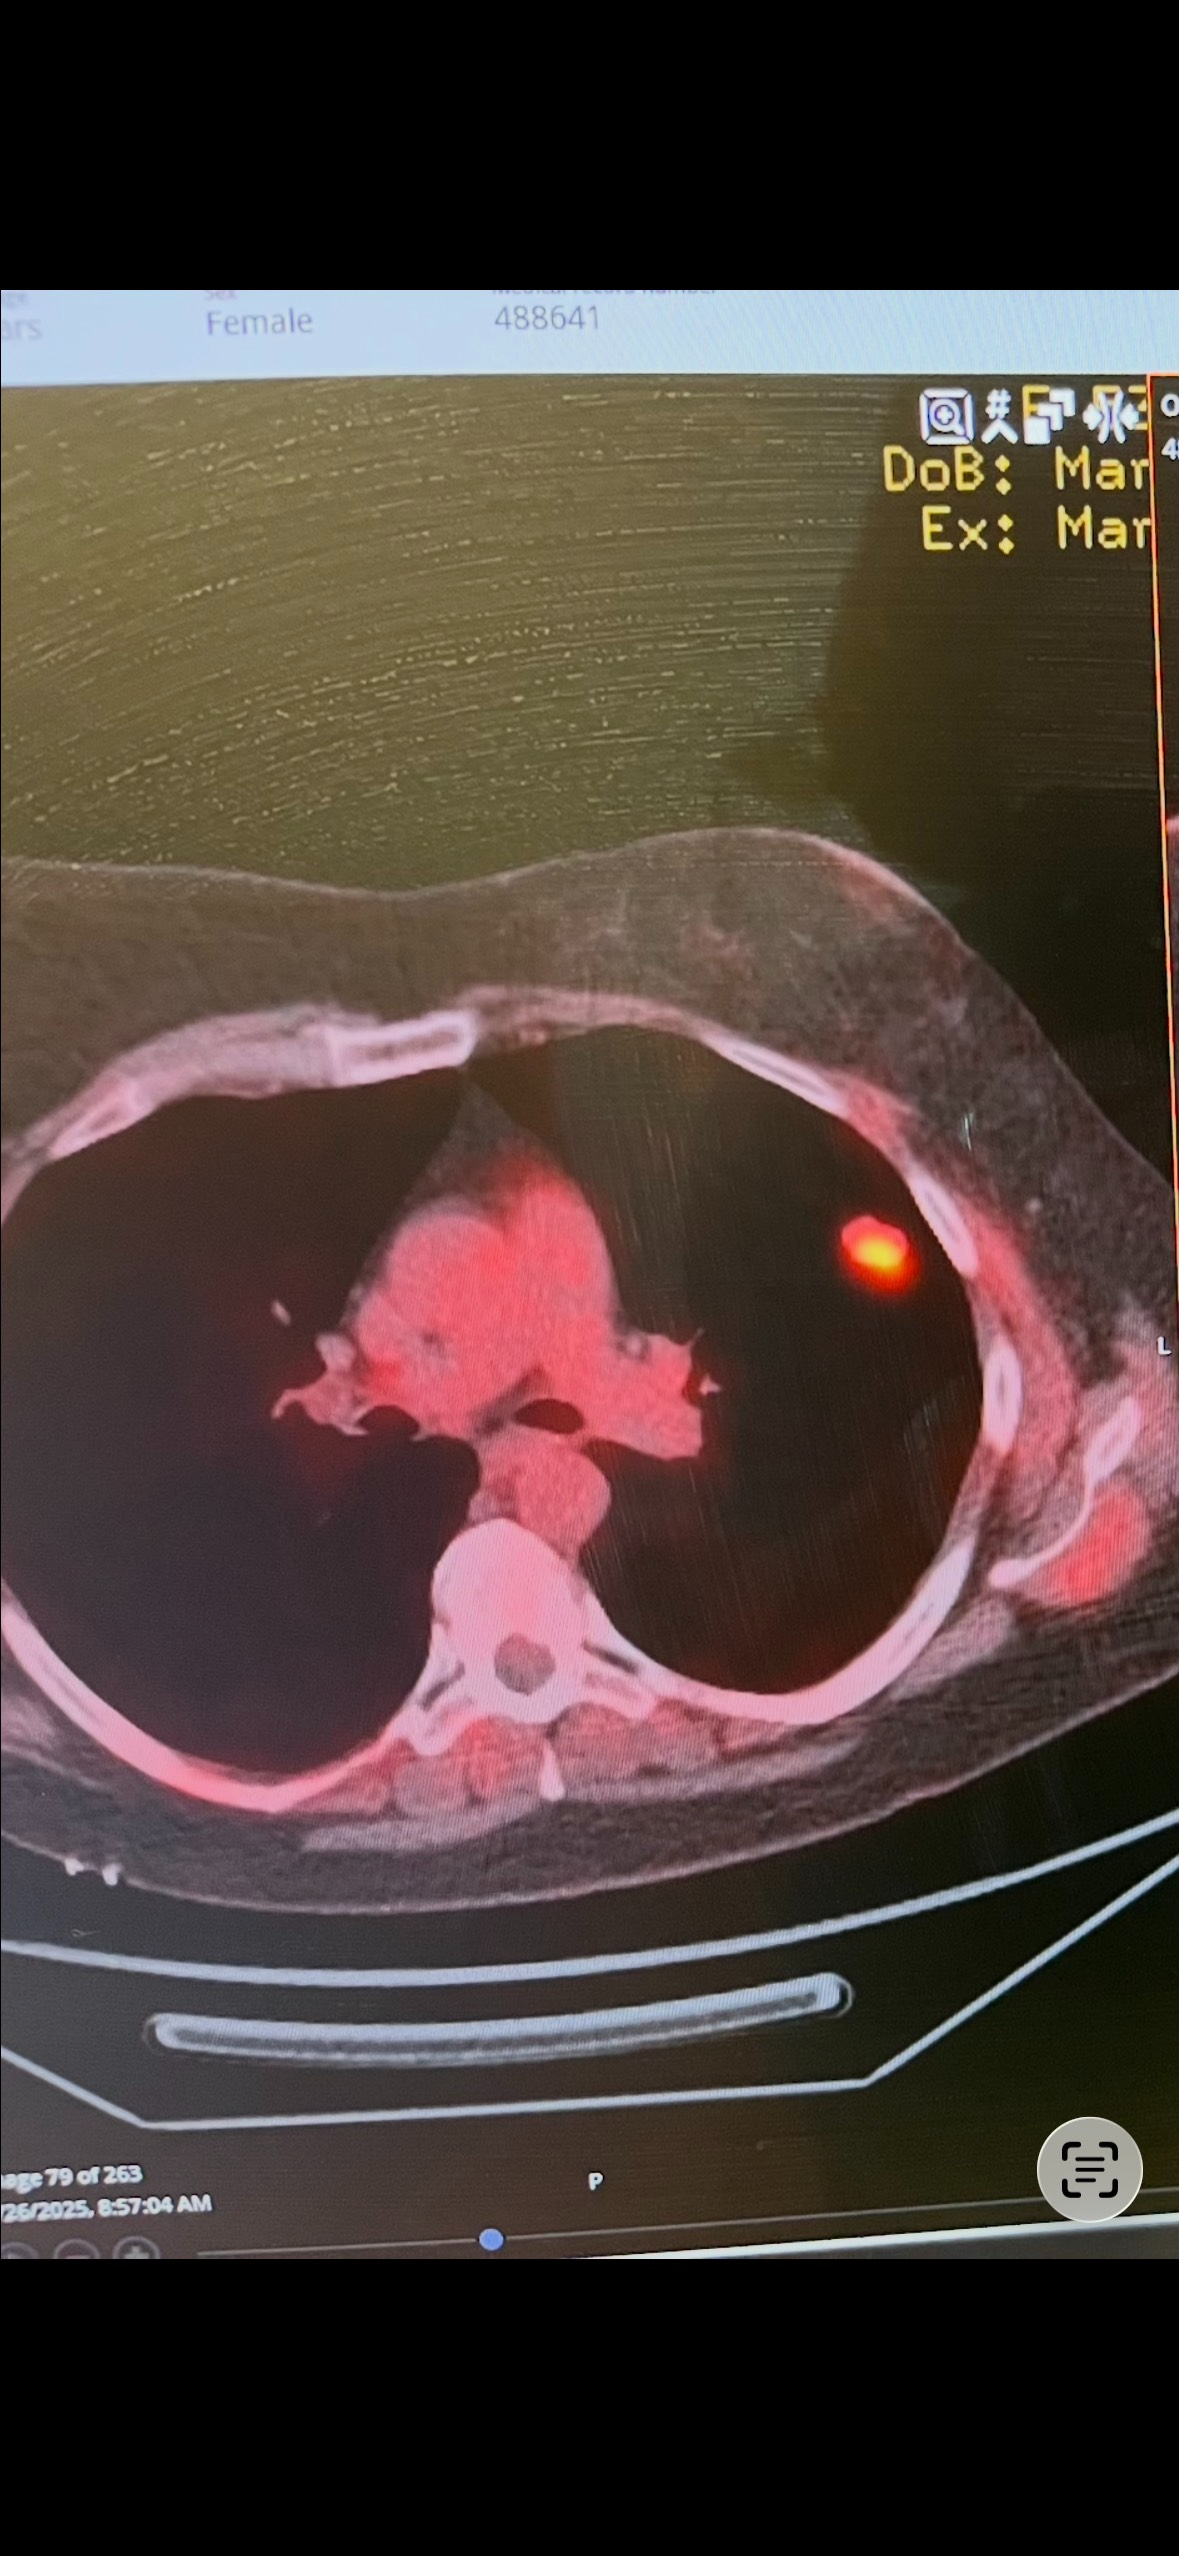

As many people may know, my mother was diagnosed with triple negative stage 3 breast cancer in 2012 and she battled that for 2 years and beat it. Then came March 2023 she lost her home and all belongings to a fire leaving her homeless, then my grandma, her mother passed away exactly 1 month later. As we move forward, there has been a lot of medical issues with grandchildren. Here we are 2025 and again, she went to er for sinus infection that caused strep & staph infections. A week later a pulmonologist called her and said that she needed to be seen. Not having any idea of what was going on except she knew she had copd, they found a nodule on her left upper lung, doing a biopsy to find out yet again another form of more aggressive cancer (SCLC). Small cell lung cancer, they put her port in and started treatment right away, 2 weeks of targeted radiation, and then on to chemo. As things progressed more and more health issues have popped up. The cancer was 1 nodule only, has not spread and is responding to the chemo and now she is doing immunotherapy. A few hospital stays several er visits, they have scheduled so many Dr appointments, specialist appointments such as ENT, Endocrinology, Rheumatology, pulmonology, pain management, Cardiology, as she has an aortic iliac bypass in her abdominal aorta. Now she is dealing with skin issues, chemo brain, pleurisy, and diabetes with her blood sugar numbers reaching 400. She is now full force diabetic on insulin and Dexcom monitor. She went from working a full-time job 40-50 hours a week to just disability. The struggle is real, has to eat certain foods, tons of testing and medications. If anyone could help in anyway, prayers, a share, or any financial contribution that would be helpful. As my sister and I try to help, it's almost impossible. The burden has overwhelmed her and she is buying her home and just sinking as we all know disability doesn't make things easy. She will use any donations for bills and household things she needs and some medications that her insurance does not cover. Again, any and all help is greatly appreciated. Thank you all!!!